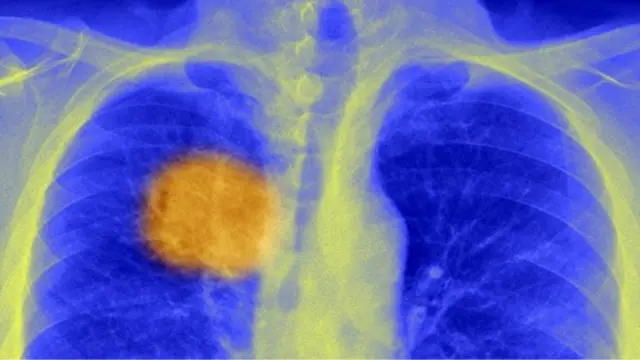

Kaynak, SPL

Fakat mutasyona uğrayarak bozulmuş bu hücrelerin çok azı gözden kaçabilir. Bunlar zamanlar bölünüp çoğalarak milyarlarca sayıya ulaşıp tümör haline gelir.

Tümör oluştuktan sonra, kanserli hücrelerin her biri yok edilinceye dek o kişide kanser var demektir. Çünkü birkaç tanesi bile sağlam kalsa hızla çoğalıp yeniden tümör oluşturabilir.

Kanser hücrelerinin hepsi birbirinden farklıdır. Bölündüklerinde mutasyona uğrayıp değişirler. Yani kanser tümöründeki hücreler genetik olarak birbirinden farklıdır. Tıpkı diğer canlıların da zamanla genetik varyasyonlar geliştirdiği gibi.

Bütün canlılarda olduğu gibi doğal seleksiyon yoluyla en güçlünün hayatta kalması süreci işlediğinden tümördeki hücreler de daha kanserli olacak şekilde evrilir.

Tümörlerin genetiğinin sürekli değişime uğraması kanserin tedavisini zorlaştırıyor.